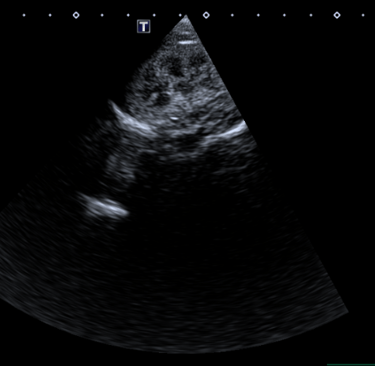

4 - Est ce que l’image obtenue vous semble correcte ?

A - Oui

B - Non

C - Je ne sais pas

5- Si non, expliquez quel réglage serait intéressant de modifier pour obtenir une image échographique correcte

A - J'ai coché oui à la réponse précédente

B - Diminuer la profondeur

C - Augmenter la profondeur

D - Augmenter le gain étagé en profondeur

E - Diminuer le gain étagé en profondeur

Question 4 : Réponse B

Question 5 : Réponse B